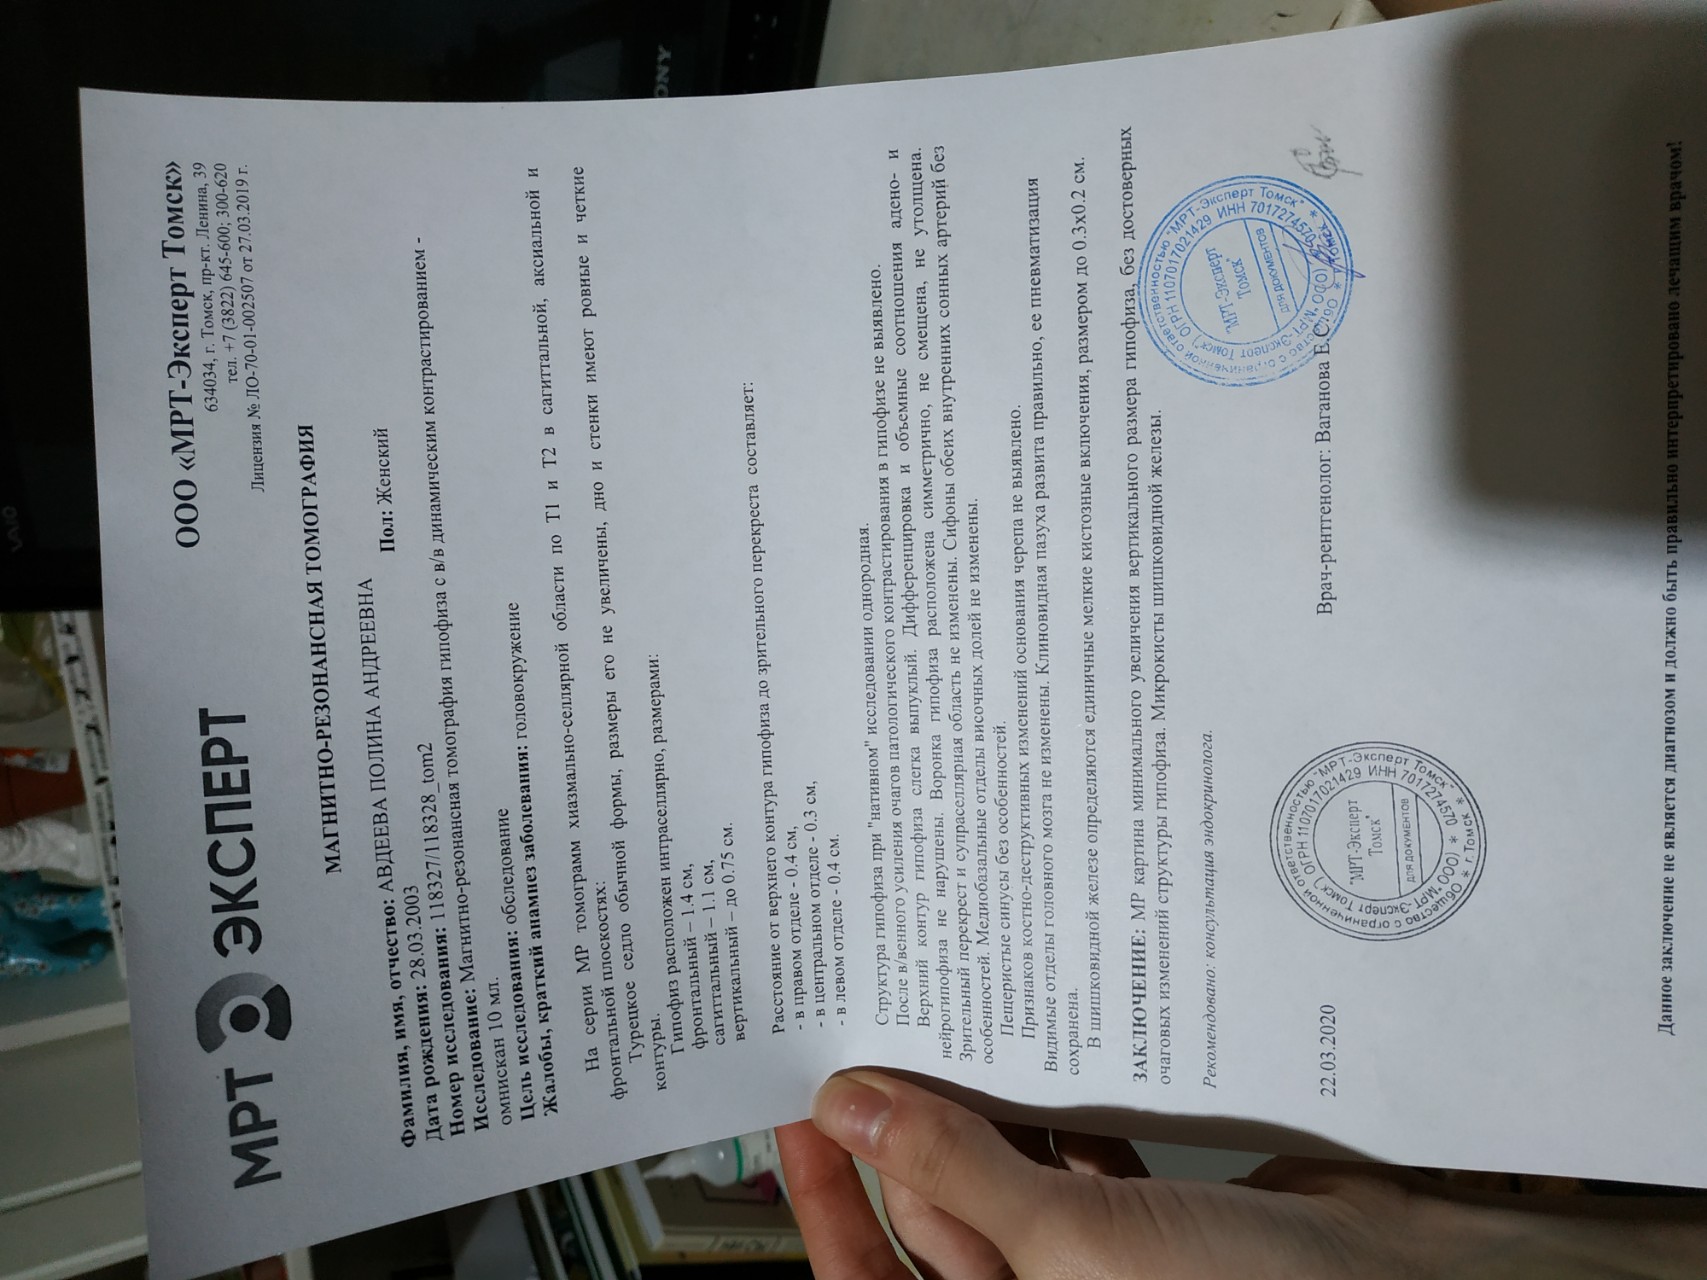

МРТ головного мозга: Расшифровка снимков и Интерпретация

Раздел: Визуальные уроки